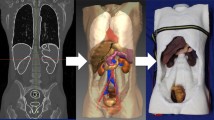

CT (computer tomography) images of ten human patients (44–72 y) with filled bladders were obtained from the University Medical Centre Mannheim, approved by the Ethical Committee II, University of Heidelberg, Germany, under the reference number: 2015-549 N-MA. As illustrated in Fig. 1, the CT images were extracted with an open-source medical image viewer (Horos™, horosproject.org, Purview, Annapolis, MD, USA), reconstructed, and exported as.stl files. The most representative bladder form was selected according to the medical experts and the model was scaled to 150 mL in volume at a relaxed state. Anatomical details, including the urethra, the interureteric bar, and the blood vessels, were designed based on cystoscopic videos in consultation with medical experts and added onto the surface of the model, using computer-aided design (CAD) software (Solidworks 2019, Dassault Systèmes Corp., Waltham, MA, USA). Three molds were designed: (1) an inner mold that matches the relaxed volume and the shape of the bladder and includes important anatomical structures, such as interureteric bar, and the vascular network; (2) an outer mold to define the thickness of the bladder wall; and (3) a urethra mold to define the shape and thickness of the urethra. In total, three different negative bladder molds (inner mold, an outer mold, and a urethra mold) were designed, as shown in Fig. 2. FlexBlad’s wall was prepared by a molding process. The outer molds being prepared in three different wall thicknesses, i.e., 2 mm, 3 mm, and 5 mm, allowed FlexBlad to have respective compliance.

The expansion of FlexBlad was examined by X-ray imaging (Uroskop Omnia, Siemens, Germany). For imaging, the contrast agent was filled in by a Foley catheter (16 Fr., 10 mL balloon inflation, Uromed, Oststeinbek, Germany). The compliance of the bladder phantom was measured using an electronic pressure sensor (SMI-1A, IntraSense™, Silicon Microstructures Inc., Milpitas, CA, USA). The sensor was mounted on a rigid stick and fixed to the bottom of the bladder phantom. Water was filled in through the soft urethra with a syringe until a total volume of 480 mL. The urethra opening was sealed with a rubber band to ensure no water leakage. The volume-pressure curve of bladder phantom with three different wall thicknesses of 2, 3, and 5 mm were measured for five times independently on each phantom, respectively. The results were averaged and plotted in Fig. 3.

Since the FlexBlad was made of silicone materials, it showed large volume expansion, as confirmed by X-ray imaging (Fig. 3a). During this exploration FlexBlad voiding under X-ray came very close to a realistic voiding cystourethrography. The expansion of the phantom was repeatedly carried out with no damage observed. The compliance of FlexBlad, defined as the volume expansion over the internal pressure increase in the unit of mL cmH2O−1,1 was measured in a range from 12.2 ± 2.8 – 32.7 ± 5.4 mL cmH2O−1 (Fig. 3c). This range covered physiological and pathological bladder compliance values. Although the values vary depending on measurement conditions and methods, physiological human bladder compliance is considered to be > 25 mL cmH2O−1.29 Compliance ratings from 12.5 – 25.0 mL cmH2O−1 are considered as intermediate bladder compliance, values below 12.5 mL cmH2O−1 are defined as poor compliance.28